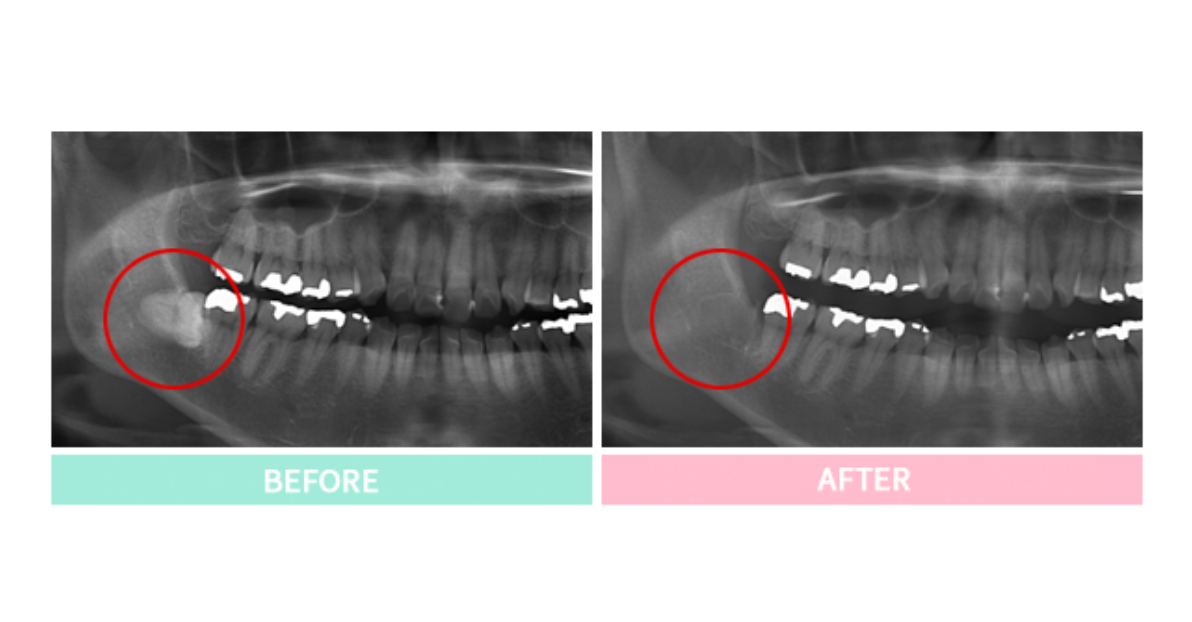

口腔外科では、親知らずの抜歯や顎関節症、口腔粘膜の異常、外傷など、さまざまな症例に対応します。特に親知らずの抜歯は、生え方によって難易度が異なり、埋まっていたり斜めに生えている場合は外科的な処置が必要です。かず歯科医院では歯科用CTを活用し、神経や血管の位置を正確に把握した上で、安全な抜歯を行います。術後の痛みや腫れをできるだけ抑えられるよう、丁寧な処置を心がけています。

また、口腔内のできものや粘膜の異常も診察し、必要に応じて検査や処置を行います。口腔内の腫瘍や嚢胞は、良性・悪性の判断が重要になるため、少しでも違和感がある場合は早めの受診をおすすめします。口腔外科の診療では、大学病院での経験を活かし、専門的な視点で診断と治療を行っています。